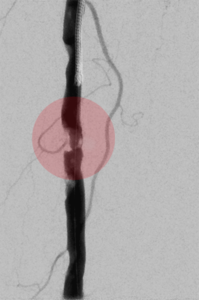

5. Thrombektomie – mechanische Entfernung von Blutgerinnseln

Wenn ein Gefäß durch Blutgerinnsel verschlossen ist, kann man den Verschluss mechanisch wiedereröffnen, indem man die Ablagerungen über spezielle Katheter absaugt. Dazu stehen uns Kathetersysteme, die mit Vakuum arbeiten bzw. zusätzlich die Gerinnsel vor dem Absaugen mit Hilfe von Wasserstrahlen oder Rotation der Katheterspitze zerkleinern, zur Verfügung.